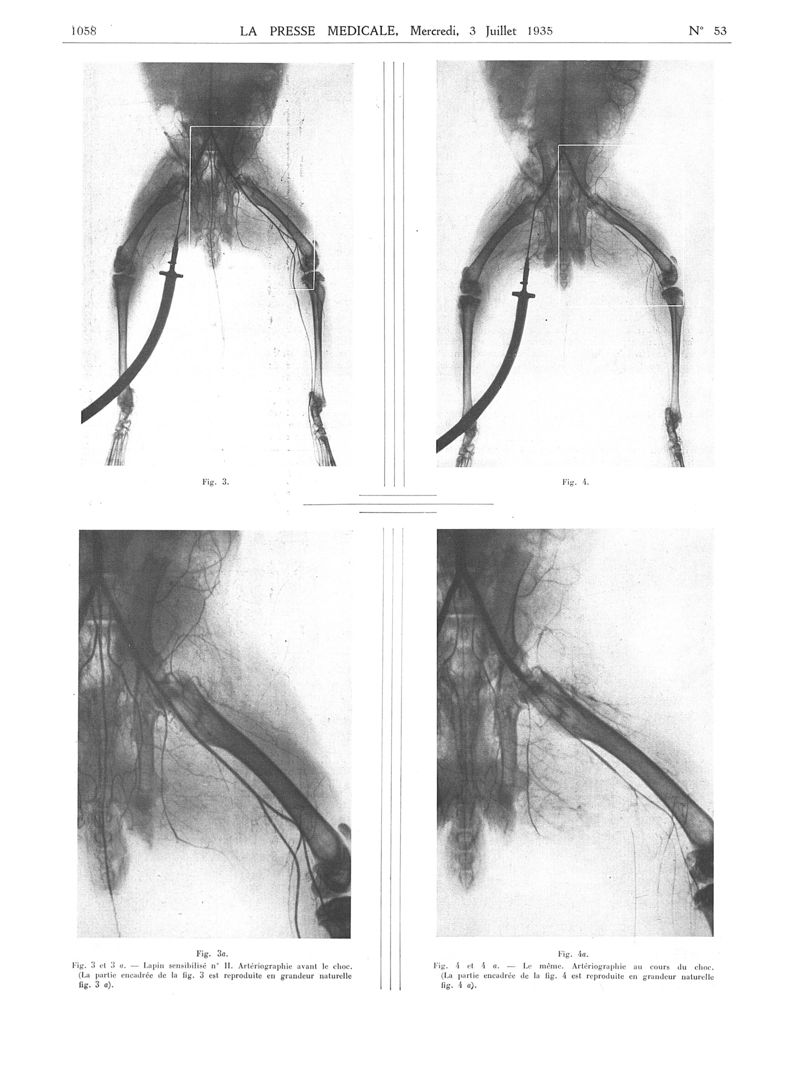

La Presse médicale - [Articles originaux]

1935, Articles originaux. - Masson et Cie, 1935.